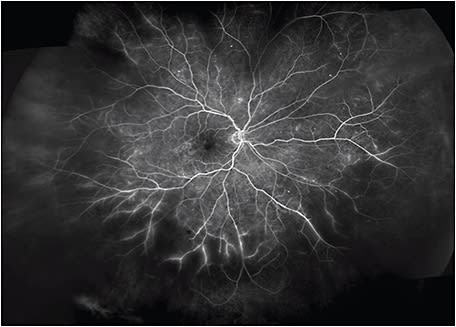

This patient was imaged with the Optos California UWF imaging device, which provides nonmydriatic panoramic fundus images with a 200° view of the retina, displaying 82% of retinal surface area in a single capture. Ultrawidefield fluorescein angiography (UWF-FA) showed microaneurysms and mild leakage at the posterior pole, and identified large areas of peripheral retinal nonperfusion (Figures 2 and 3). Given these results, the severity of this DR changed from mild to severe NPDR. The management was changed accordingly from follow-up to panretinal photocoagulation (PRP).

In this case, UWF fundus imaging enabled the detection of key lesions indicative of DR and large areas of retinal ischemia outside the 7F boundary. Based on the traditional grading scale, the severity of this case had initially been underestimated. However, UWF-FA data graded this DR as severe NPDR, which led to earlier treatment and closer follow-up.